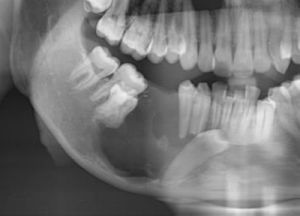

頜骨囊腫在X線平片上表現為圓形或卵圓形密度減低區,邊界清楚,邊緣光滑銳利,其內可以是單房或多房。隨著囊液積聚,囊腫具有一定的膨脹性,可引起臨近牙移位,少數可見牙吸收。周圍骨質吸收,囊腔壁為緻密白線(骨皮質線)。

頜骨囊腫治療方法術後半年複查曲面斷層片,囊腔外形輪廓改變,囊腔體積變小,囊壁與鄰近結構如牙齒、上頜竇、下牙槽神經管的距離變化,腔內密度增高,有不同程度的新骨形成,在囊腫周圍可見放射狀骨小梁結構。開窗減壓的優點是該手術一般在局麻下完成,手術簡單,創傷小,風險低,經濟性好,術後復發率低,患者痛苦少,尤其是保留了頜骨原有的完整性,咀嚼功能不受影響,甚至膨隆的頜骨隨時間的推移也慢慢恢復正常,大大提高了患者的生存質量,患者容易接受。頜骨囊腫治療方法開窗減壓術在臨床套用中有一定適應證,對於單囊及多囊性的較大的牙源性頜骨囊腫,只需開一個視窗,即可達到治療目的。但對於囊壁突破骨皮質,周圍組織嚴重移位和頜骨嚴重變形的囊腫,不主張套用此方法。總之,此術作為治療較大頜骨囊腫的一種辦法,值得推廣。